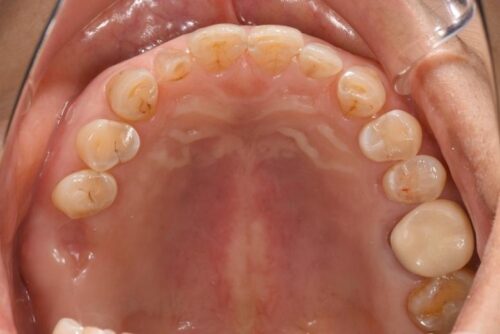

さて今回は、奥歯のインプラント治療の症例を紹介します。

【治療前】

【治療後】

| 治療内容 | 上顎奥歯のインプラント治療 |

| 治療期間 | 2ヶ月 |

| 治療費用 | 31万円( 税抜 ) |

| 副作用・リスク | 外科処置が伴うため、術後の疼痛・腫脹・出血・咬合痛などを生じる事があります。 麻酔を行う場合、腫れやむくみを生じる事があります。 また、被せ物や土台が外れたり、欠けたり、緩んだりする事があります。 |